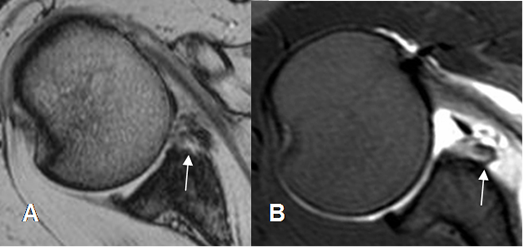

Fig 62. Lesión de Bankart.

A y B: RM axial en FFE. Alteración en la parte antero-inferior del labrum por lesión de Bankart.